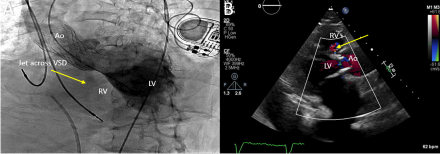

Case Description: An 80-year-old woman with history of hypertension, HFpEF, and TAVR 8 months prior for severe aortic stenosis (AS) at an outside hospital presented with worsening dyspnea and peripheral edema over the past month. Blood pressure was 148/53mmHg, heartrate 83bpm, oxygen saturation 98% and auscultation revealed a harsh holosystolic murmur 4/6 loudest at left sternal border and bibasilar rales. Chest X-ray showed pulmonary edema and bilateral pleural effusions. NT-proBNP was 17,000pg/ml and troponin-I was negative. Echocardiogram showed EF55-60%, a membranous VSD, severe pulmonary hypertension, and moderate paravalvular leak (PVL). Coronary angiogram showed non-obstructive disease. Right heart catheterization confirmed significant left to right shunting.

Treatment/Outcomes: Cardiothoracic surgery was consulted for multidisciplinary evaluation, and joint recommendation was for surgical aortic valve replacement and VSD closure which was successfully performed. One month follow-up echocardiogram showed normal aortic valve gradient without PVL and normal right ventricular pressure.

Discussion/Conclusion: Numerous potential risks such as severe and uneven calcification of the native valve, an elliptic aortic annulus, excessive valve sizing, or elevated valve placement can lead to VSD. A recurrent element in many of these instances involves direct trauma to the septum caused by the implanted valve, exacerbated by subsequent annulus dilation. The presence of PVL is common post-TAVR and is an established independent prognostic factor, while VSD post-TAVR is uncommon, but may be associated with low implantation position relative to the aortic annulus or post-implantation balloon dilatation. Rarely, worsening VSD may require operative management. In this case, the improvement of heart failure symptoms and echocardiogram parameters after transthoracic surgery confirmed successful repair.